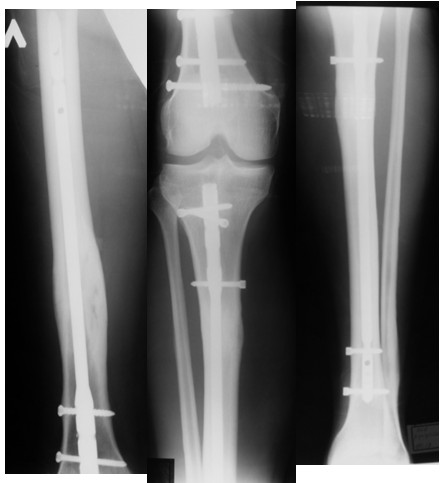

Рентгенограммы пациента со сросшимися переломами пястных костей, большеберцовой и бедренной костей после остеосинтеза

Функциональный результат у пациента со сросшимися переломами пястных костей, большеберцовой и бедренной костей после остеосинтеза